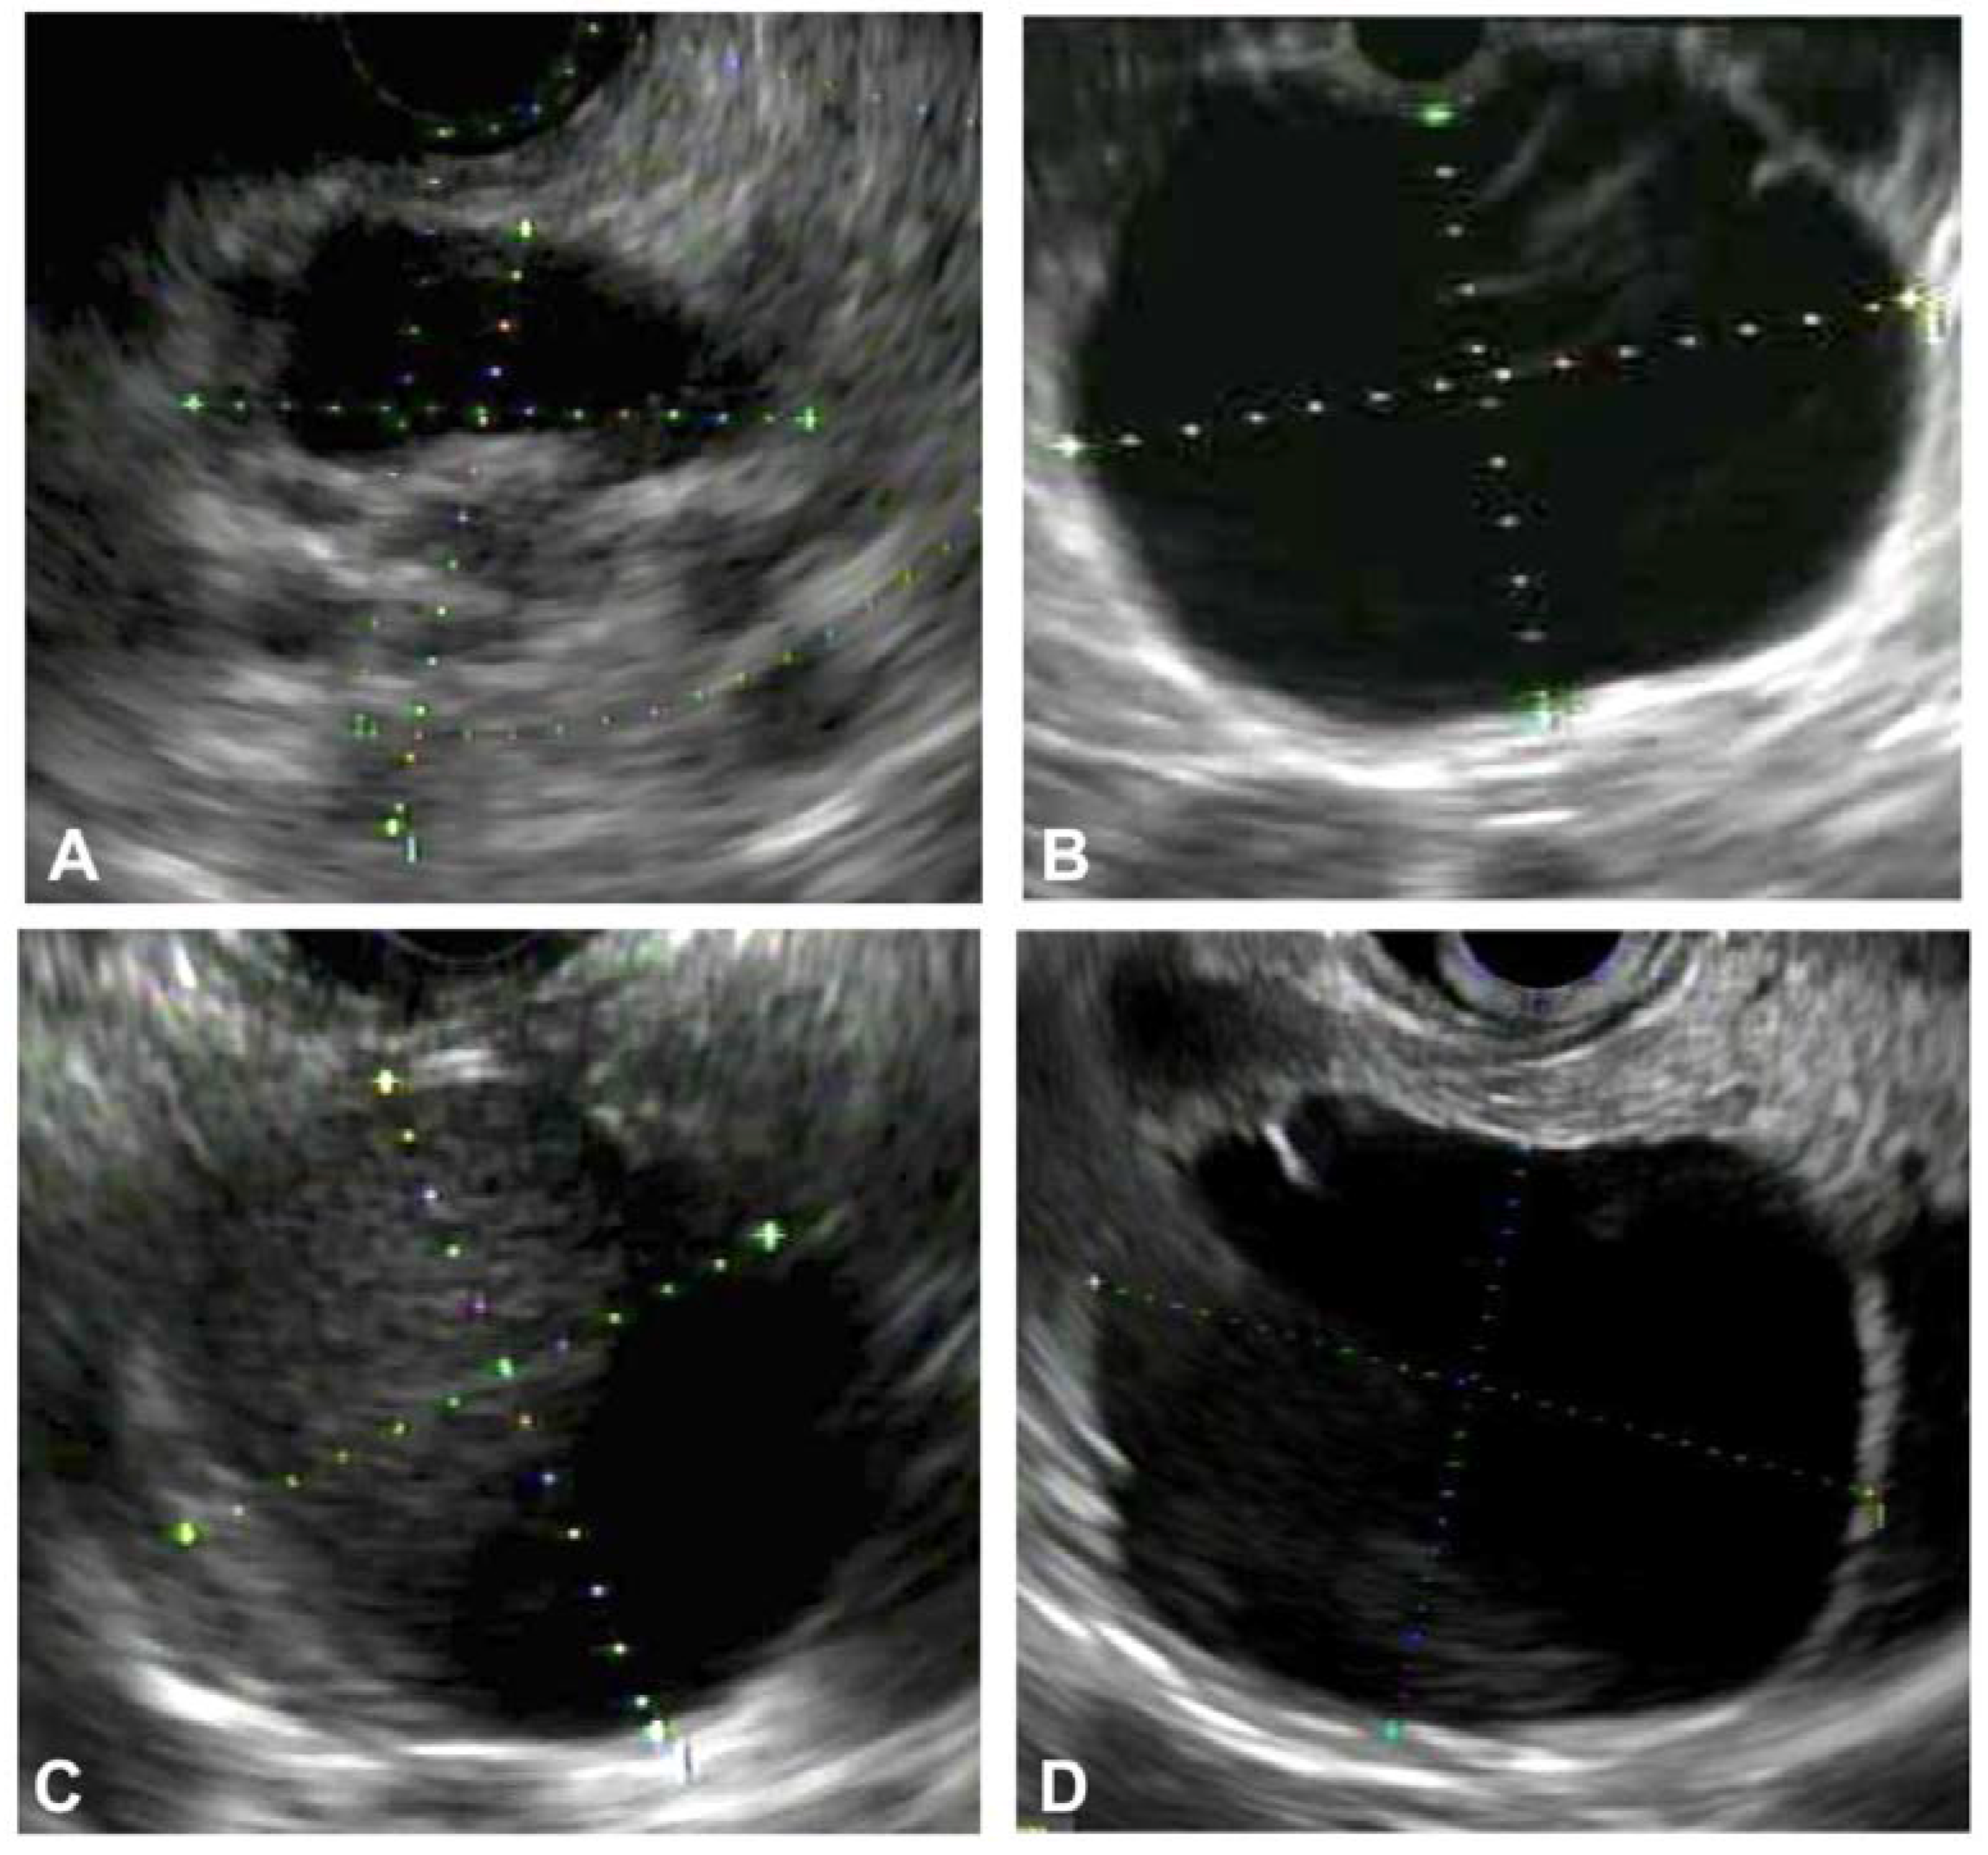

3.1. EUS Imaging and Morphology in the Differentiation of PCLs

3.2.1. Advances in Endosonographic Imaging for Defining Cyst Morphology (Diagnosis and Risk Stratification)

Contrast-Harmonic Mode Endoscopic Ultrasound